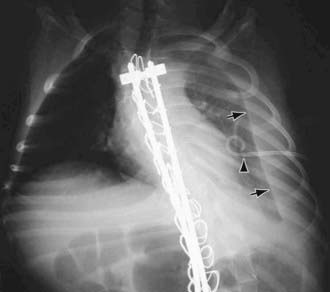

image

Figure 409-2 Left chylothorax (arrows) following spinal fusion with Harrington rods. It is postulated that the thoracic duct was injured during spine surgery. The pigtail chest tube (arrowhead) needed to be retracted to better drain the effusion.